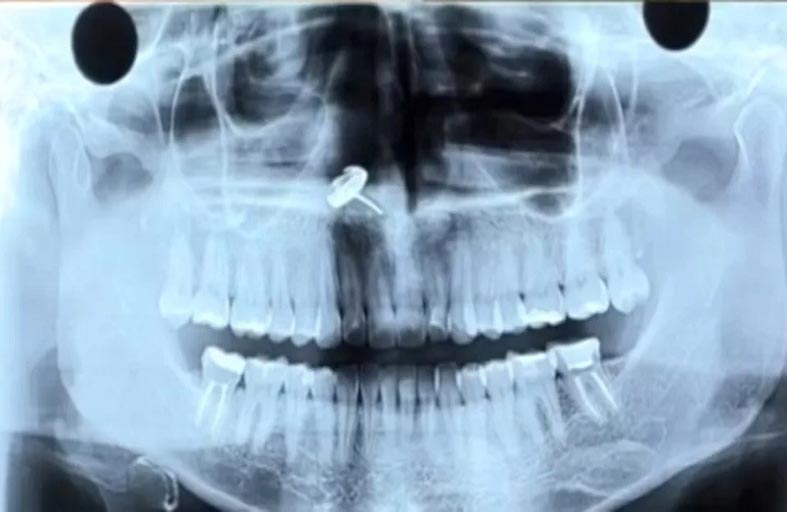

كشفت امرأة برازيلية شابة قصة العثور على قرط عالق في أنفها عن غير قصد لسنوات بعد استنشاقه على ما يبدو أثناء نومها.

وتقول المؤثرة فرناندا كوكيت (28 عاماً) إن القرط عُثر عليه عندما أجرى طبيب أسنانها تصويراً بالأشعة السينية على فكها قبل إجراء عملية لإزالة أحد أسنانها العلوية.

وفي البداية، اعتقد طبيب الأسنان أن فرناندا نسيت إزالة حلق الأنف قبل إجراء الصورة، لكن عندما أخبرته أنها لا تضع حلقاً في أنفها أبداً، نصحها بالذهاب إلى المستشفى.

وأوضحت فرناندا لمتابعيها "بالنسبة لأولئك الذين أزالوا ضرس العقل، فأنت تعلم أنه يتعين القيام بالتصوير بالأشعة السينية البانورامية".

وبعد حدوث الارتباك الأولي، قال أخصائيو الأنف والحنجرة إنهم اضطروا إلى إجراء عملية جراحية على الفور لإزالة قطعة المجوهرات وقطع النسيج الميت - أو النخر - من حوله.

وأضافت فرناندا "ذهبت إلى المستشفى وأكد طبيب الأنف والأذن والحنجرة أن لديّ جسم غريب داخل أنفي". وتمت إزالة القرط من خلال الجراحة، مع اعتقاد الفتاة البالغة من العمر 28 عاماً أنها لا بد أنها استنشقت القرط أثناء النوم.